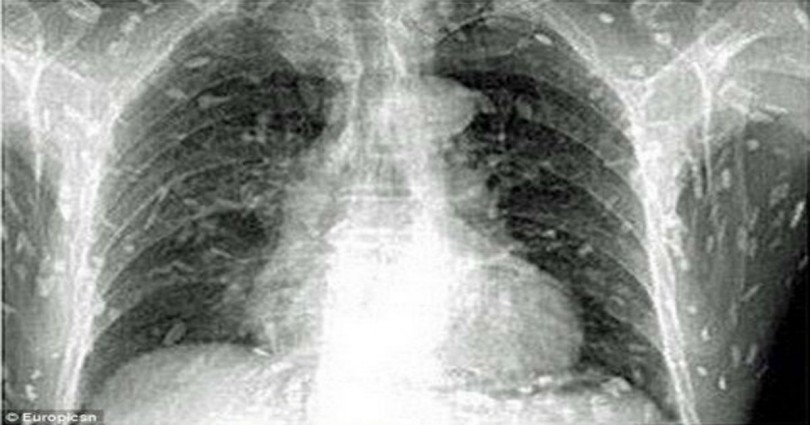

Τα σκουλήκια κυριολεκτικά κατέλαβαν το σώμα του. Όταν είδε τις ακτινογραφίες του, του κόπηκαν τα πόδια..

Όταν είδε τις ακτινογραφίες του, του κόπηκαν τα πόδια.. Σκουλήκια του έτρωγαν τα σωθικά και ο λόγος κάτι που πολλοί από εμάς τρώμε κάποιες φορές! – Εικόνα4 Μία μόλυνση από σκουλήκια-ταινίες μπορεί να οδηγήσει σε κυστικέρκωση. Αυτό συμβαίνει όταν τα σκουλήκια καταφέρνουν να μπουν στην κυκλοφορία του αίματος! Μετά μπορούν να πάνε στον εγκέφαλο, με κίνδυνο της ίδιας της ζωής του ασθενή.